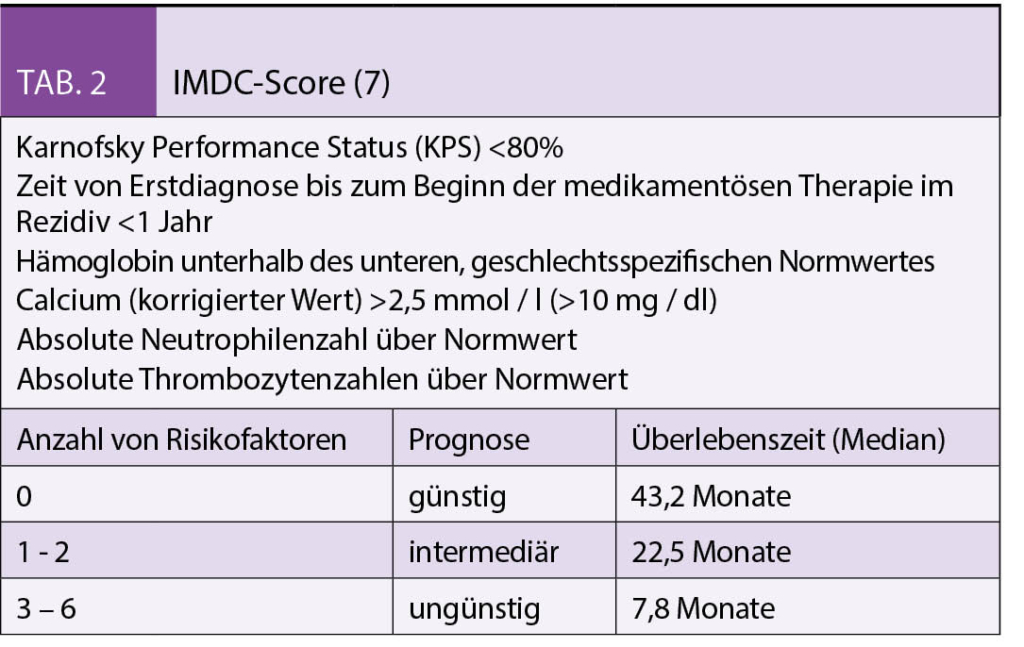

Risikofaktoren des metastasierten Nierenzellkarzinoms

Die metastasierten Tumorstadien werden in die Risikogruppen niedriges, intermediäres und hohes Risiko anhand definierter prognostischer Faktoren eingeteilt. Jedem Risikofaktor wird ein Punkt gegeben. Neben dem Motzer-Score (Tab. 1) wird aktuell vorwiegend der International Metastatic Renal-Cell Carcinoma Database Consortium (IMDC) (Tab. 2) Score zur Einteilung angewendet (6-7).